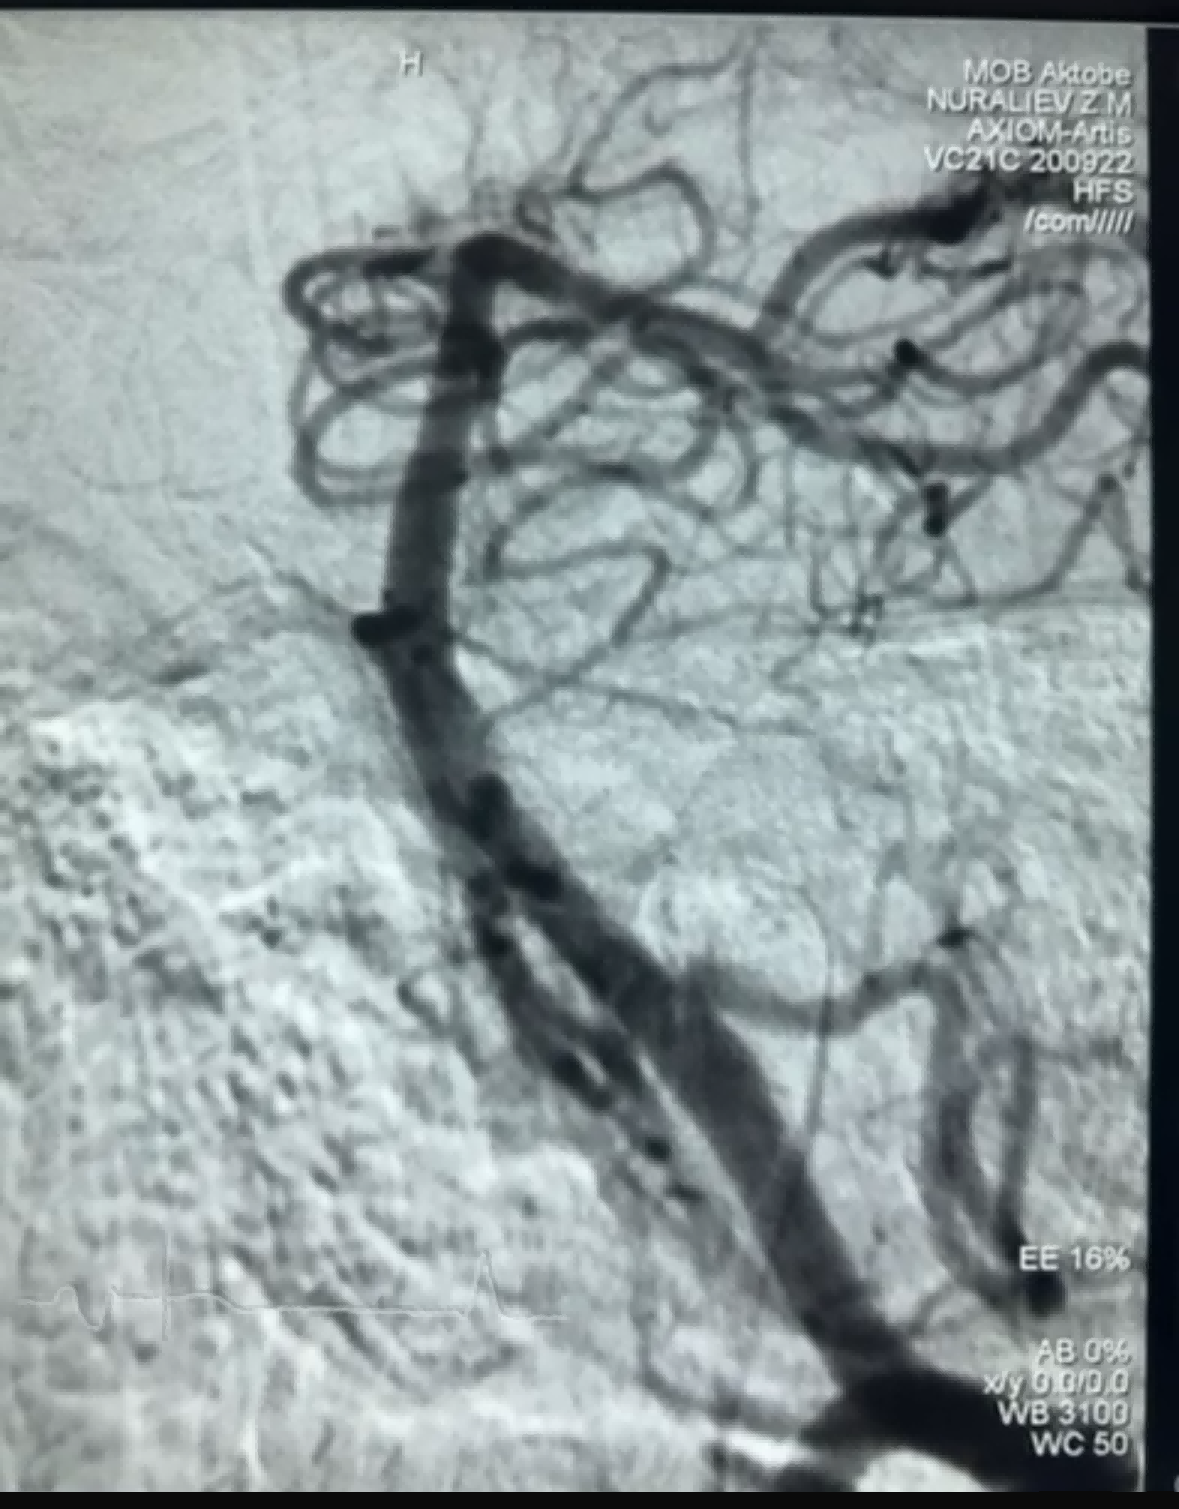

Наскоро имаше успешен случай на тромбектомия с помощта на Dredger Stent Retriever на NeuroSafe Medical Co., Ltd. Dredger Stent Retriever има неинвазивен мек връх, който значително намалява риска от увреждане на интимата, и има уникален отвор със специална форма дизайн, който улавя кръвни съсиреци главно чрез затягане на промените на празнината.